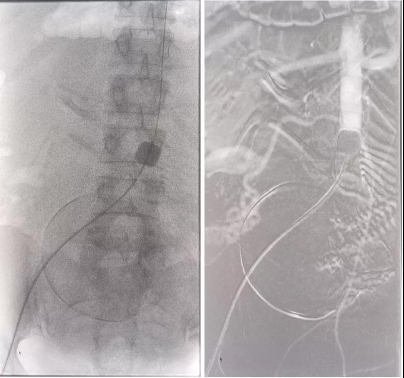

the operation of pernicious placenta previa completed with balloon occlusion of abdominal aorta

Surgical treatment of pernicious placenta previa with IUD pregnancy under uterine artery embolization

Pregnancy complicated with pelvic vein thrombosis, the operation was completed after inferior vena cava filter placement.